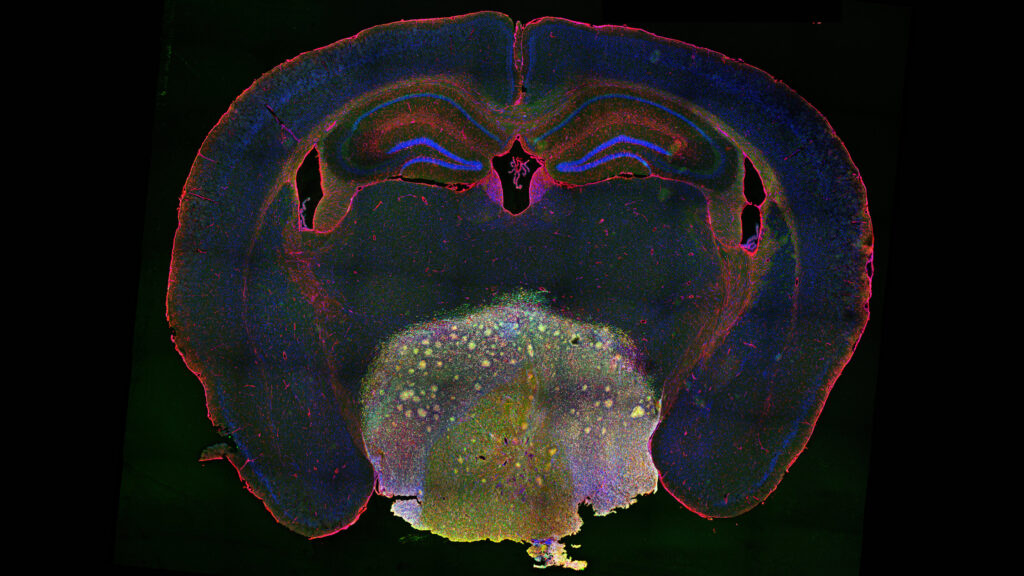

Highly invasive tumor hijacks neurons to grow, but a common heart medication offers hope

Chinese researchers have revealed new insights into the growth of craniopharyngioma and identified a potential therapeutic treatment. Their findings are published online in Science Translational Medicine.